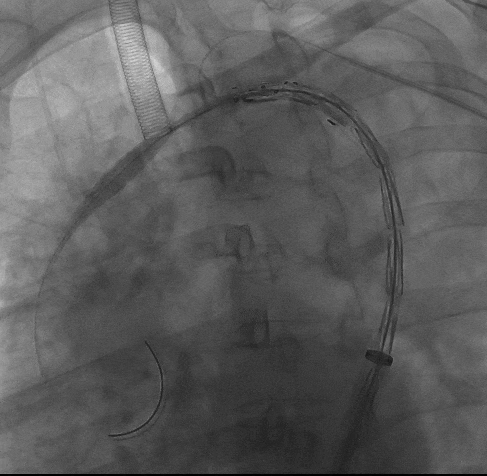

3、再次造影确认支架位置准确后,快速释放主体支架,助手配合牵拉分支导丝释放分支支架。

动脉长鞘怎么置入宁波市第二医院血管外科运用Castor®单分支支架结合长鞘建立导丝通路的方法治疗Stanford B型胸主动脉夹层一例_https://www.jmylbn.com_新闻资讯_第10张

释放主体支架

动脉长鞘怎么置入宁波市第二医院血管外科运用Castor®单分支支架结合长鞘建立导丝通路的方法治疗Stanford B型胸主动脉夹层一例_https://www.jmylbn.com_新闻资讯_第11张

牵拉分支导丝释放分支